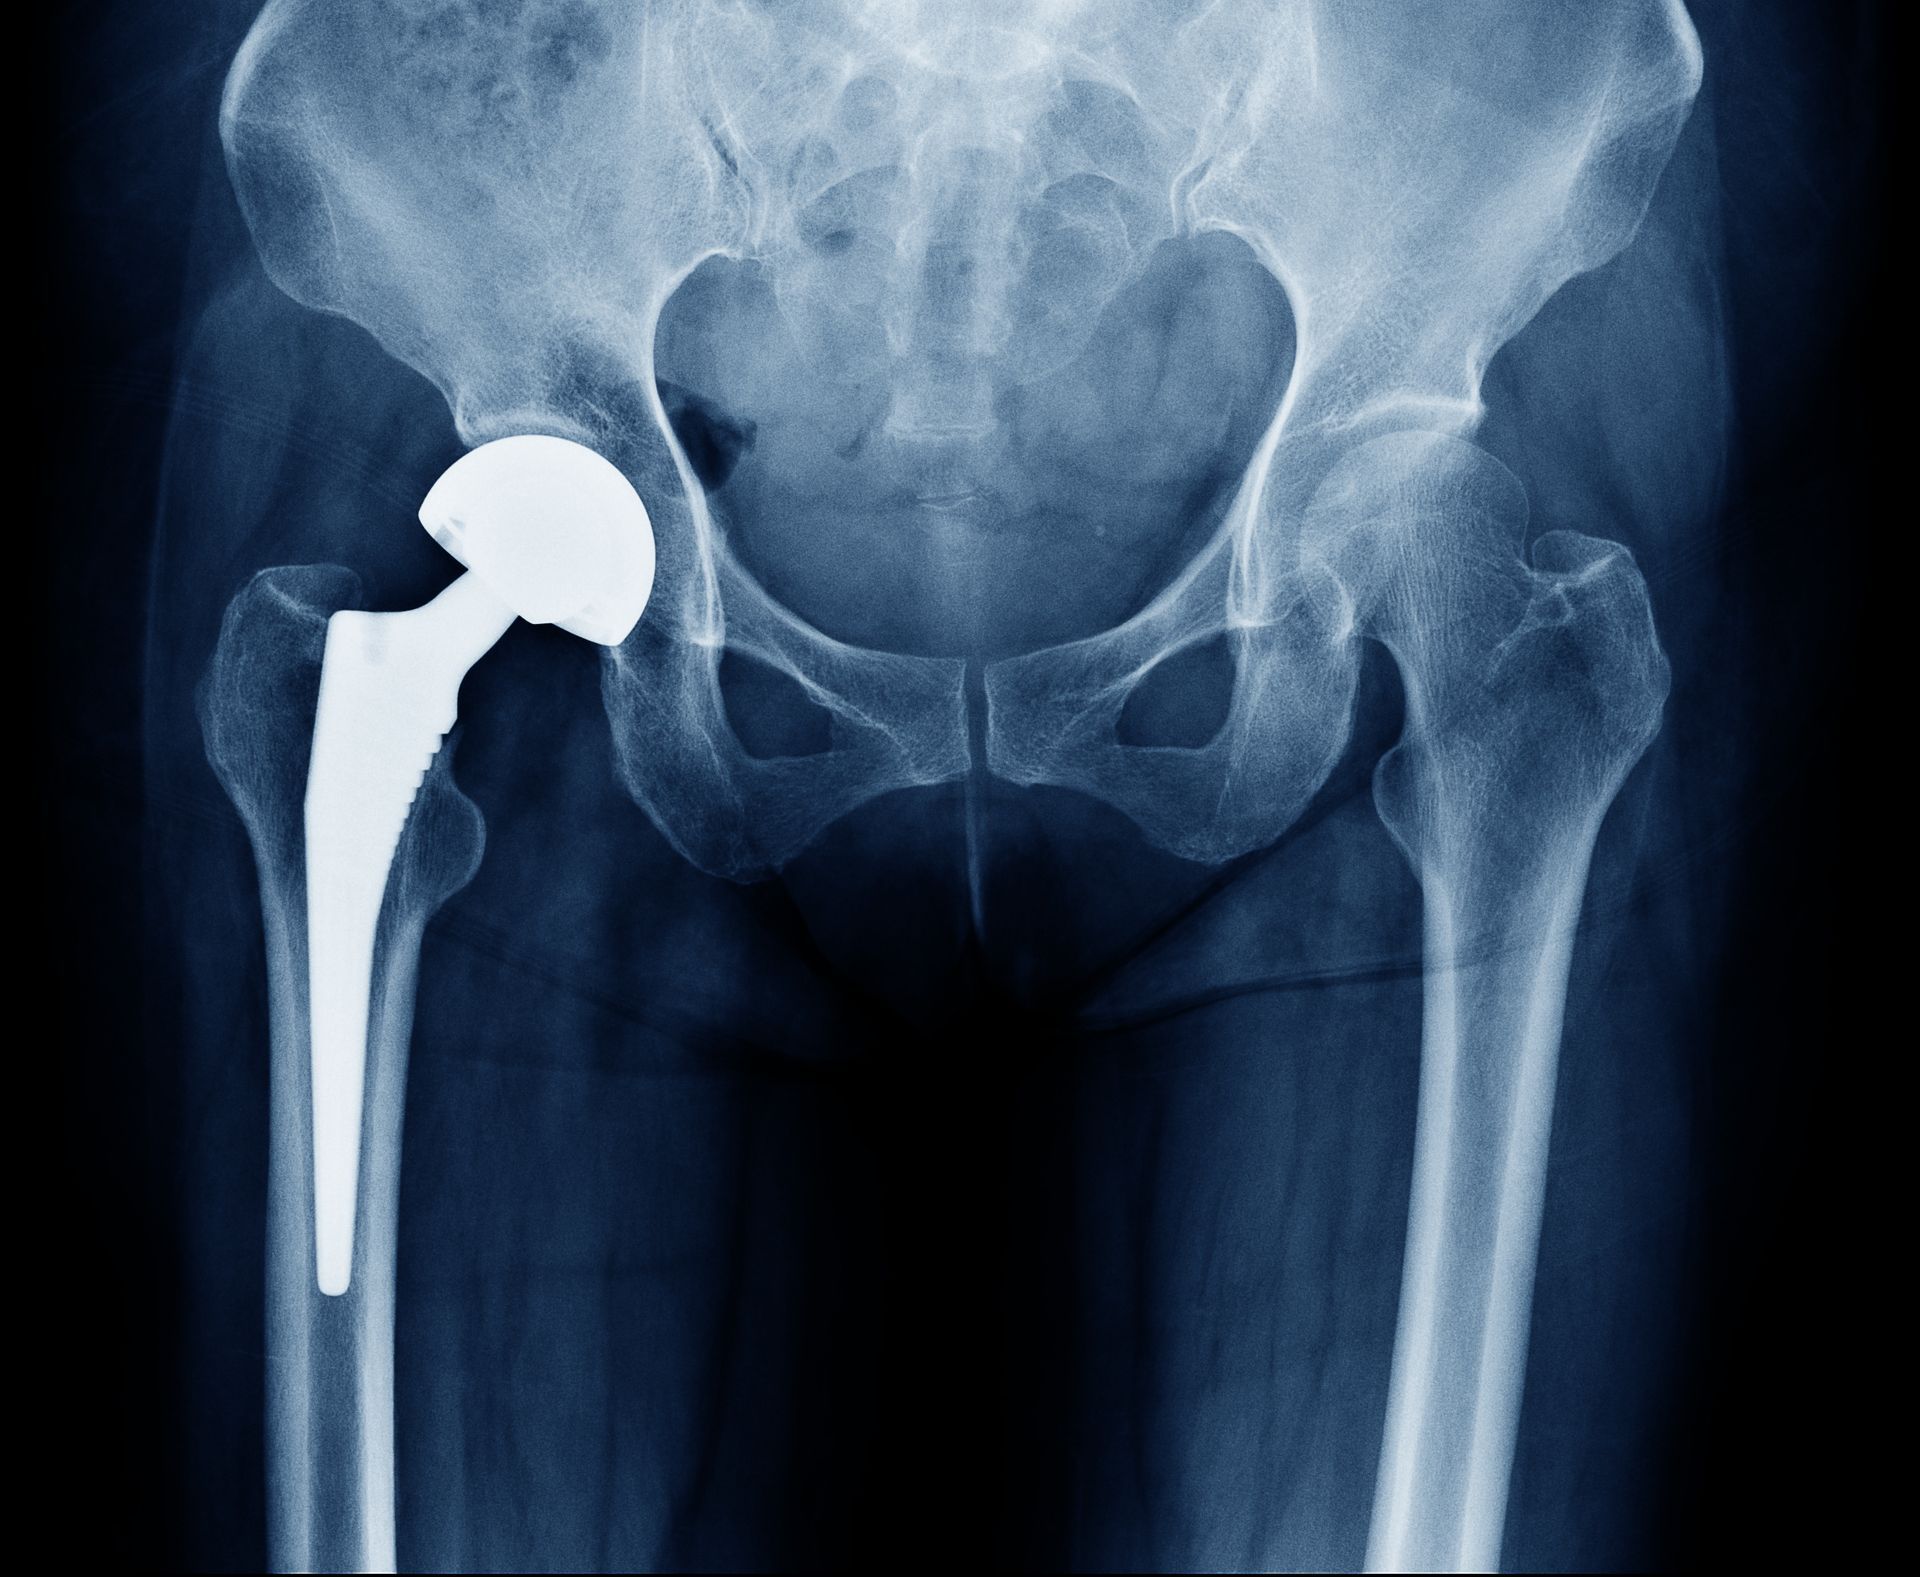

Com mais de 5000 cirurgias realizadas e mais de 1500 artroplastias de sucesso, meu compromisso é ajudar pacientes a recuperarem sua qualidade de vida, combinando competência técnica com valores de seriedade e honestidade.